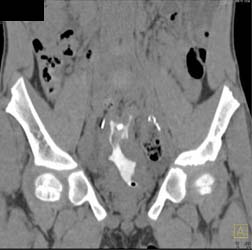

Bladder Cancer